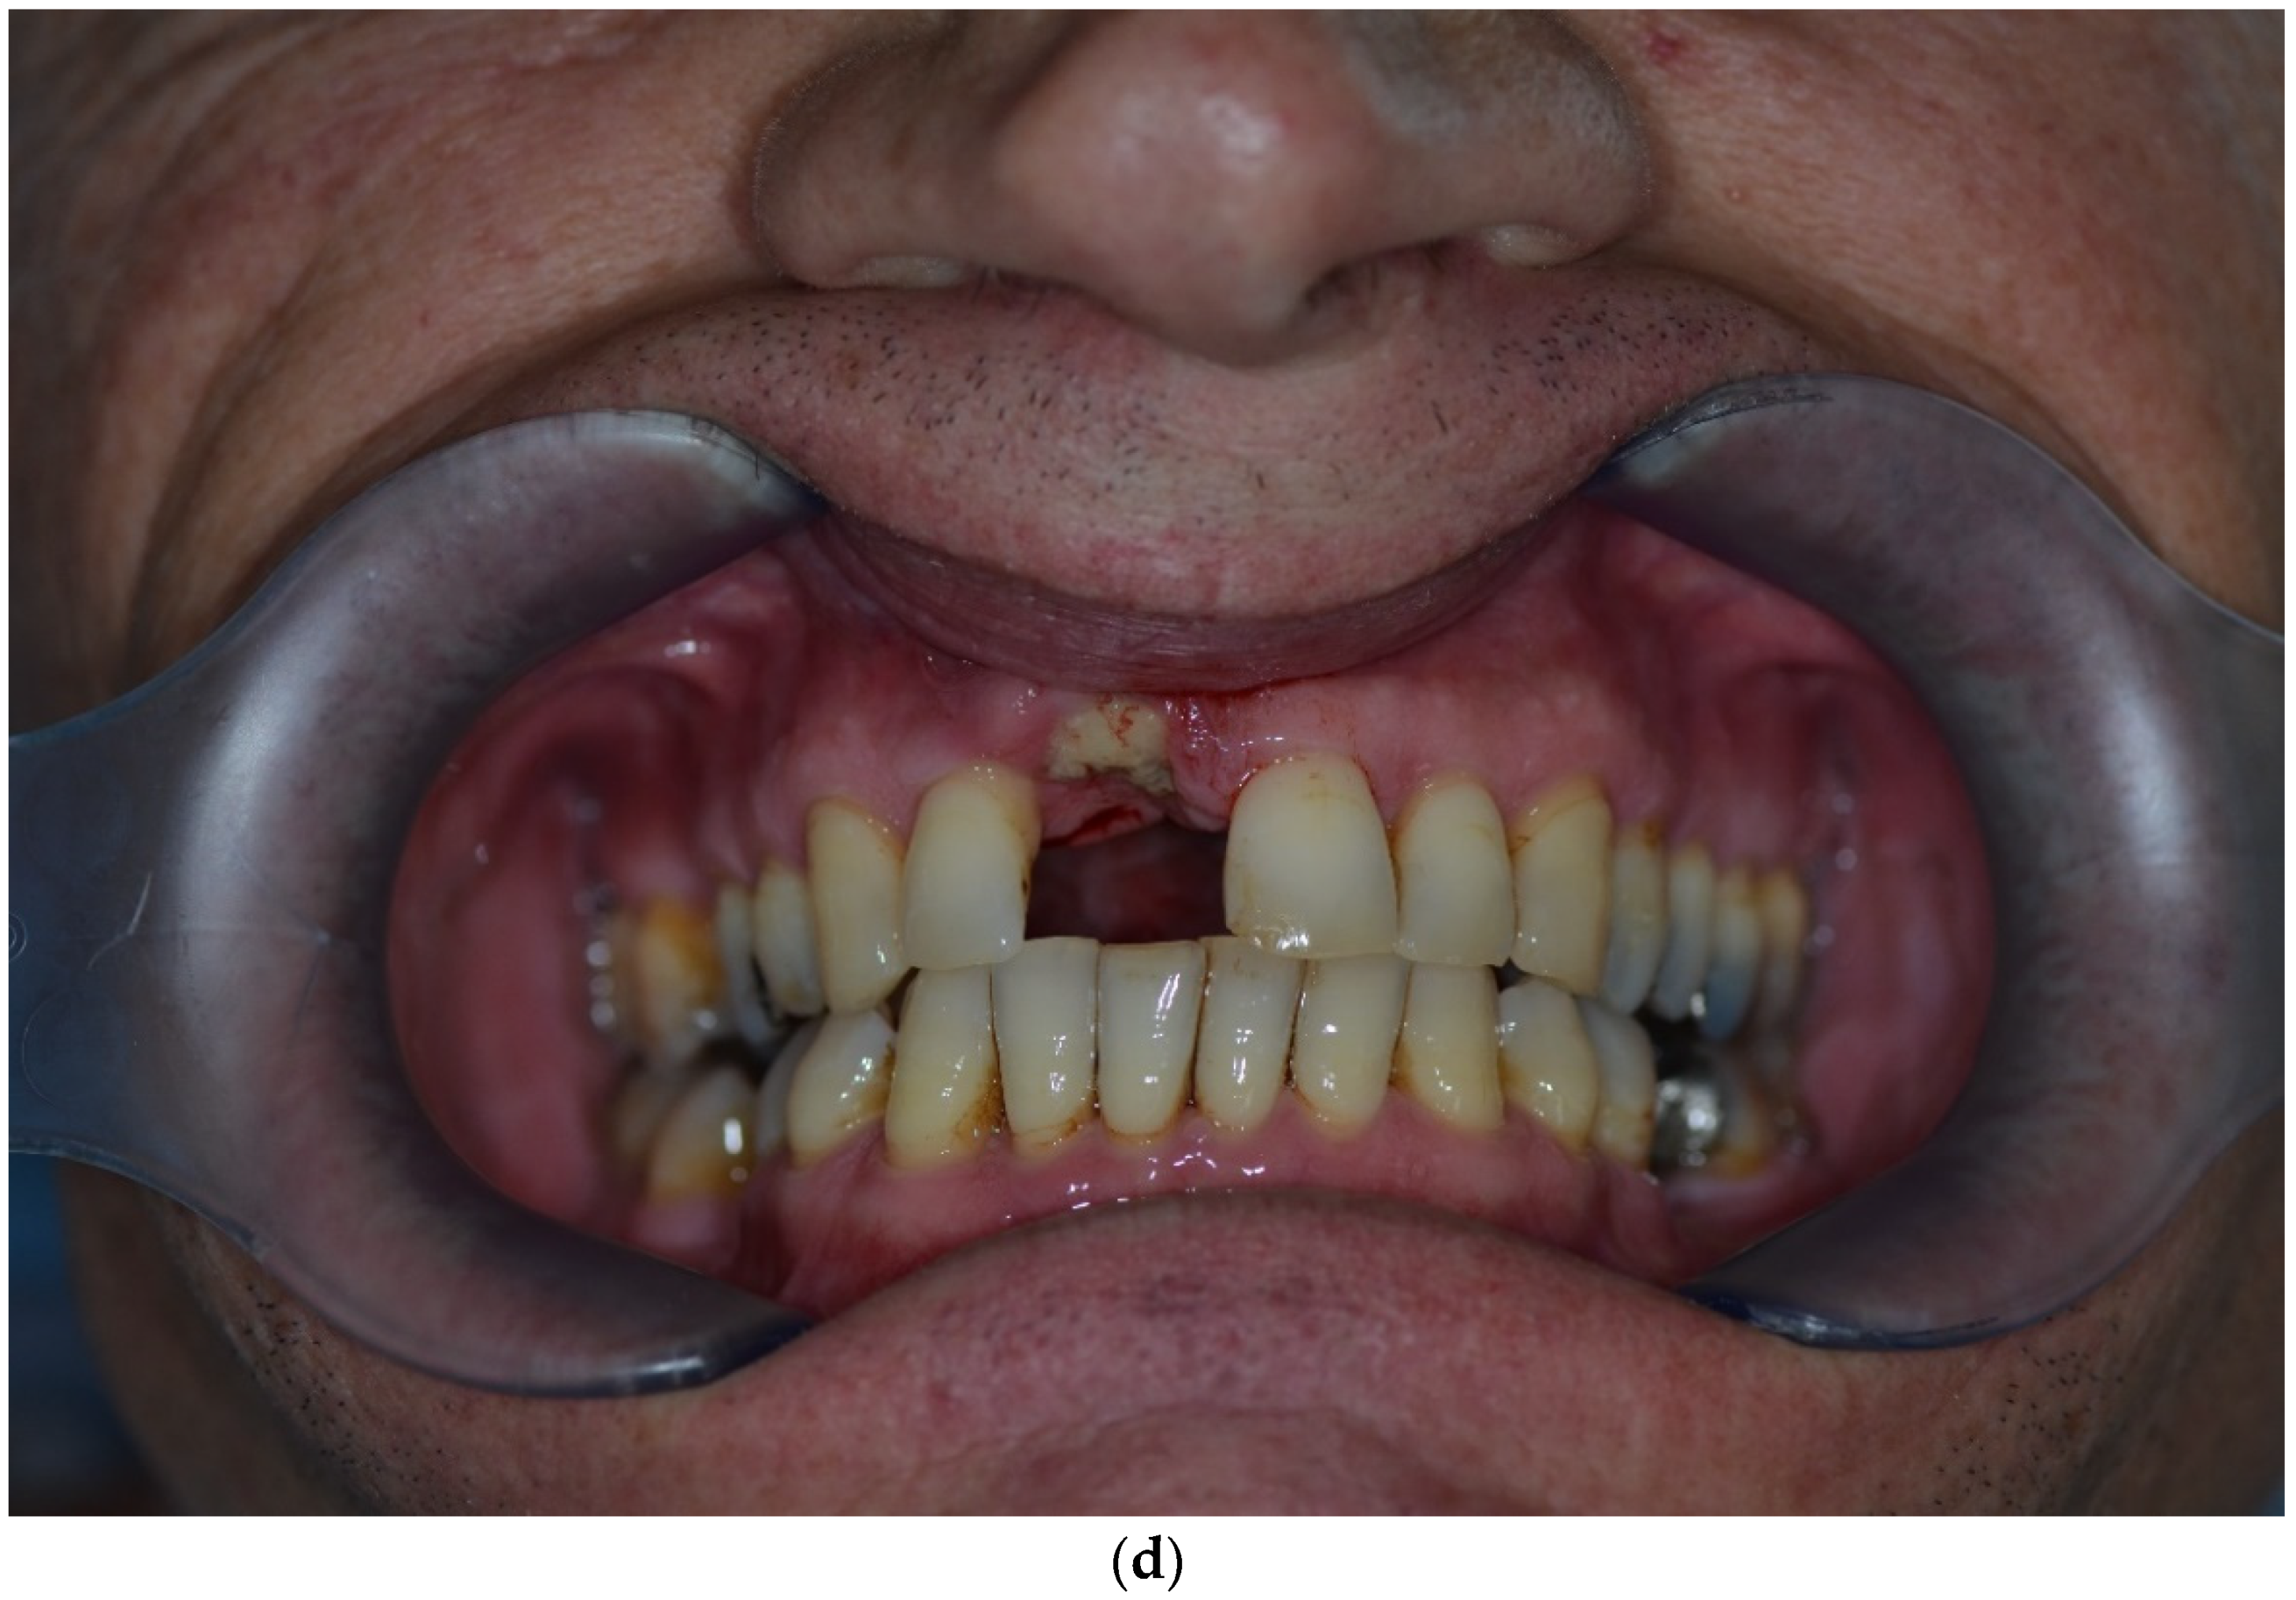

Clinical example of over-contouring. (a) Class III defect with pronounced vestibular deficit and minor vertical deficit. (b) Post-OP: Attachment of a cortico-cancellous allogeneic bone block. Vestibular over-contouring with the cortical plate and vertical over-contouring of the block can be seen. The block protrudes over the limbus alveolaris, i.e., over the bone border of the adjacent teeth. (c) After 5 months: the over-contoured portion of the cortical portion of the block was not resorbed, but part of the cancellous portion of the block was palatally resorbed away. (d) The over-contoured block penetrates the mucosa. The cortical portion is revealed.